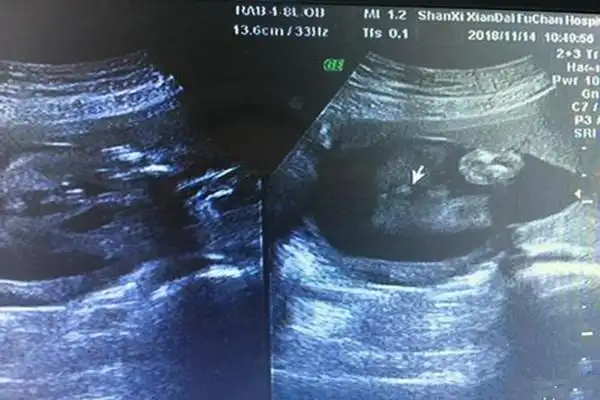

今天刚做的nt,有经验的宝妈猜一猜,男宝还是女宝?

孕26周四维下睾丸的样子 如何看四维彩超识性别